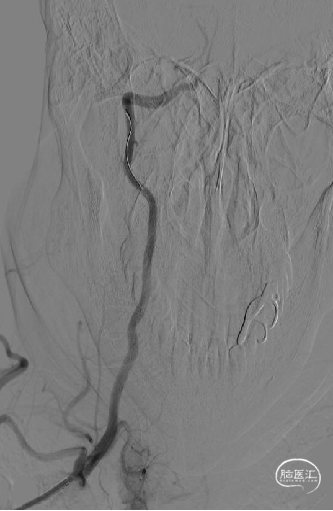

造影示支架完全覆盖狭窄段,与血管壁贴合良好。复查脑血管造影颅内远端血流通畅。

术后影像

术前影像